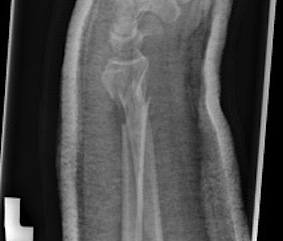

Distal Radius Fracture K wires APplateex fixbridge plate